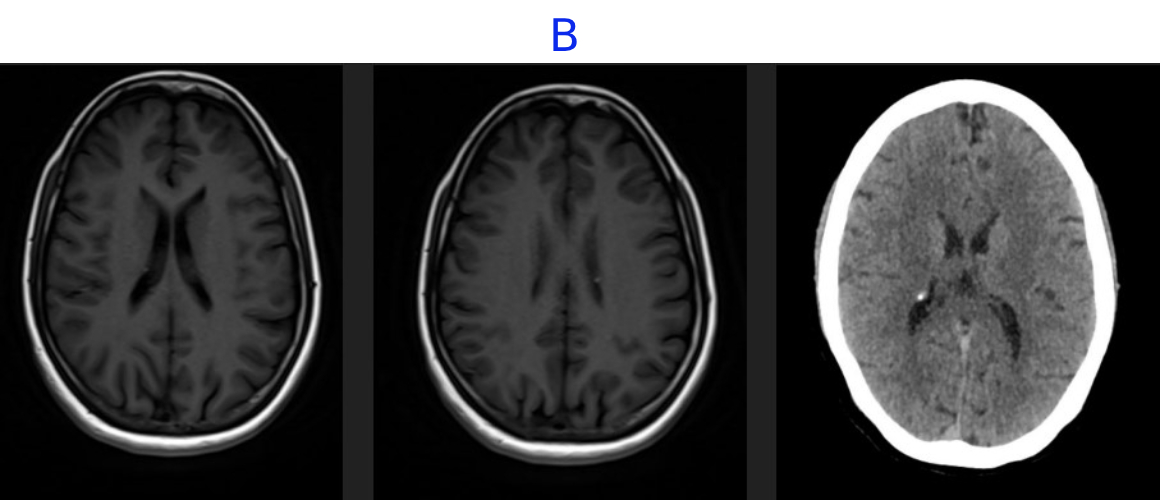

• B. MR AND CT BRAIN

• B. Multiple small subependymal nodules are seen along the margins of the bilateral lateral ventricles with few showing calcification on correlative CT.